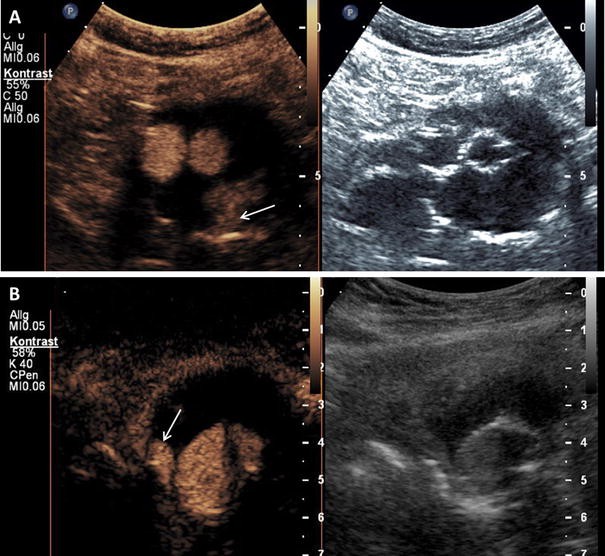

Endoleak after endovascular aortic aneurysm repair on CEUS imaging. a Typ 2 endoleak with enhancement of the aneurysm sac (arrow) caused by retrograde flow form a lumbar artery on CEUS imaging (left side) and corresponding B-mode ultrasound (right side). b Typ 1 endoleak with enhancement of the aneurysm sac (arrow) by an incomplete seal at the proximal end of the graft (main body) on CEUS imaging (left side) and corresponding B-mode ultrasound (right side)